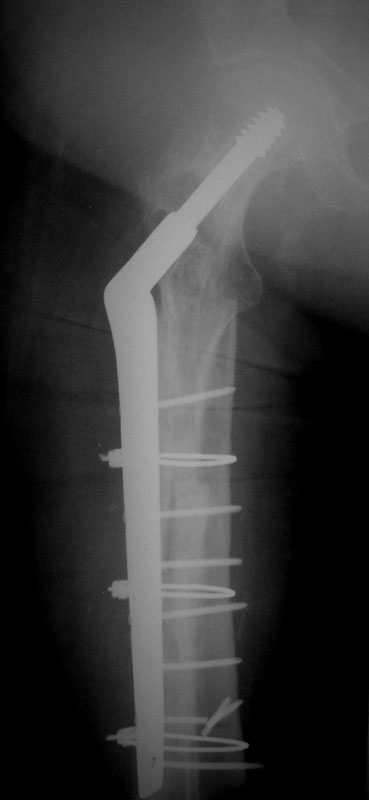

These are the Xrays of a 73 y/o women. The name of each file has the date it was taken and the view. These are all outside films and I know they are limited studies but I think the problem is evident. She had polio at age 5. 20 years ago she had a subtroch fracture plated with a DHS type implant. In Feb, 02 she presented to a local orthopod with a fracture under the plate. The hardware was loose at that time. The local orthopod kept the hardware and cabled allograft to the femur. She did well and was walking with only a cane or occ a walker until last month when she felt something was different and had some pain. She went to her orthopod who took the xrays in May. The orthopod sent her to me then. She has no motors of any significant function below the hip including lacking hip ext and flex. She has mild pain with rotational stress of the femur. She has a thick but not obese leg (she did grow up here in Wisconsin). She wears an AK brace on her leg. She has some pain but it s not too bad. She still can walk but does most of her ambulation with a wheelchair. She has little or no pain in the wheelchair. She is a 1 pack/ smoker for years. She has well controlled hypertension.

02/02/02 AP

02/02/02 lat